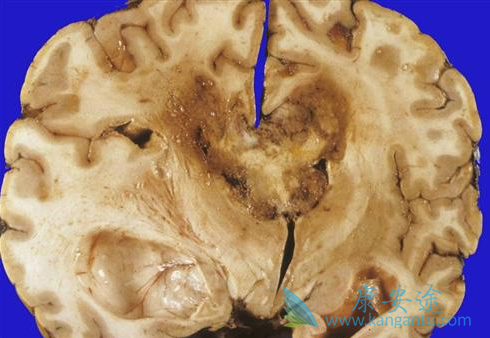

于是,美国斯坦福大学医学院的Abdulrazag Ajlan等探索使用<5mg/kg/周剂量的贝伐单抗治疗GBM,其结果发表于2017年6月《J Neurooncol》在线上。作者回顾性分析2005至2014年间80例符合入选标准、接受过贝伐单抗治疗的胶质瘤母细胞瘤患者临床资料;将患者分为低剂量组(<3mg/kg/周)和高剂量组(>3mg/kg/周)。33例患者接受低剂量治疗,47例患者接受高剂量治疗,用药2-41个周期,平均8个周期。

采用NCI不良事件标准对阿瓦斯汀治疗过程中发生的并发症进行分级,NCI不良事件标准分级3级以上为严重不良反应。35例(44%)出现与药物相关的并发症,其中以高剂量组为明显,包括胃肠道不良反应(5%)、血栓形成(3.8%)、高血压(1.3%)、咽旁脓肿(1.3%)、颅内出血(1.3%)和3例患者死亡,其中2例肺栓塞和1例胃穿孔的严重事件;而低剂量组未见严重不良反应发生(p<0.01)(表1)。两组患者的OS无明显差异,但是阿瓦斯汀高剂量组的OS有低于低剂量组的趋势,17.3个月比39个月。